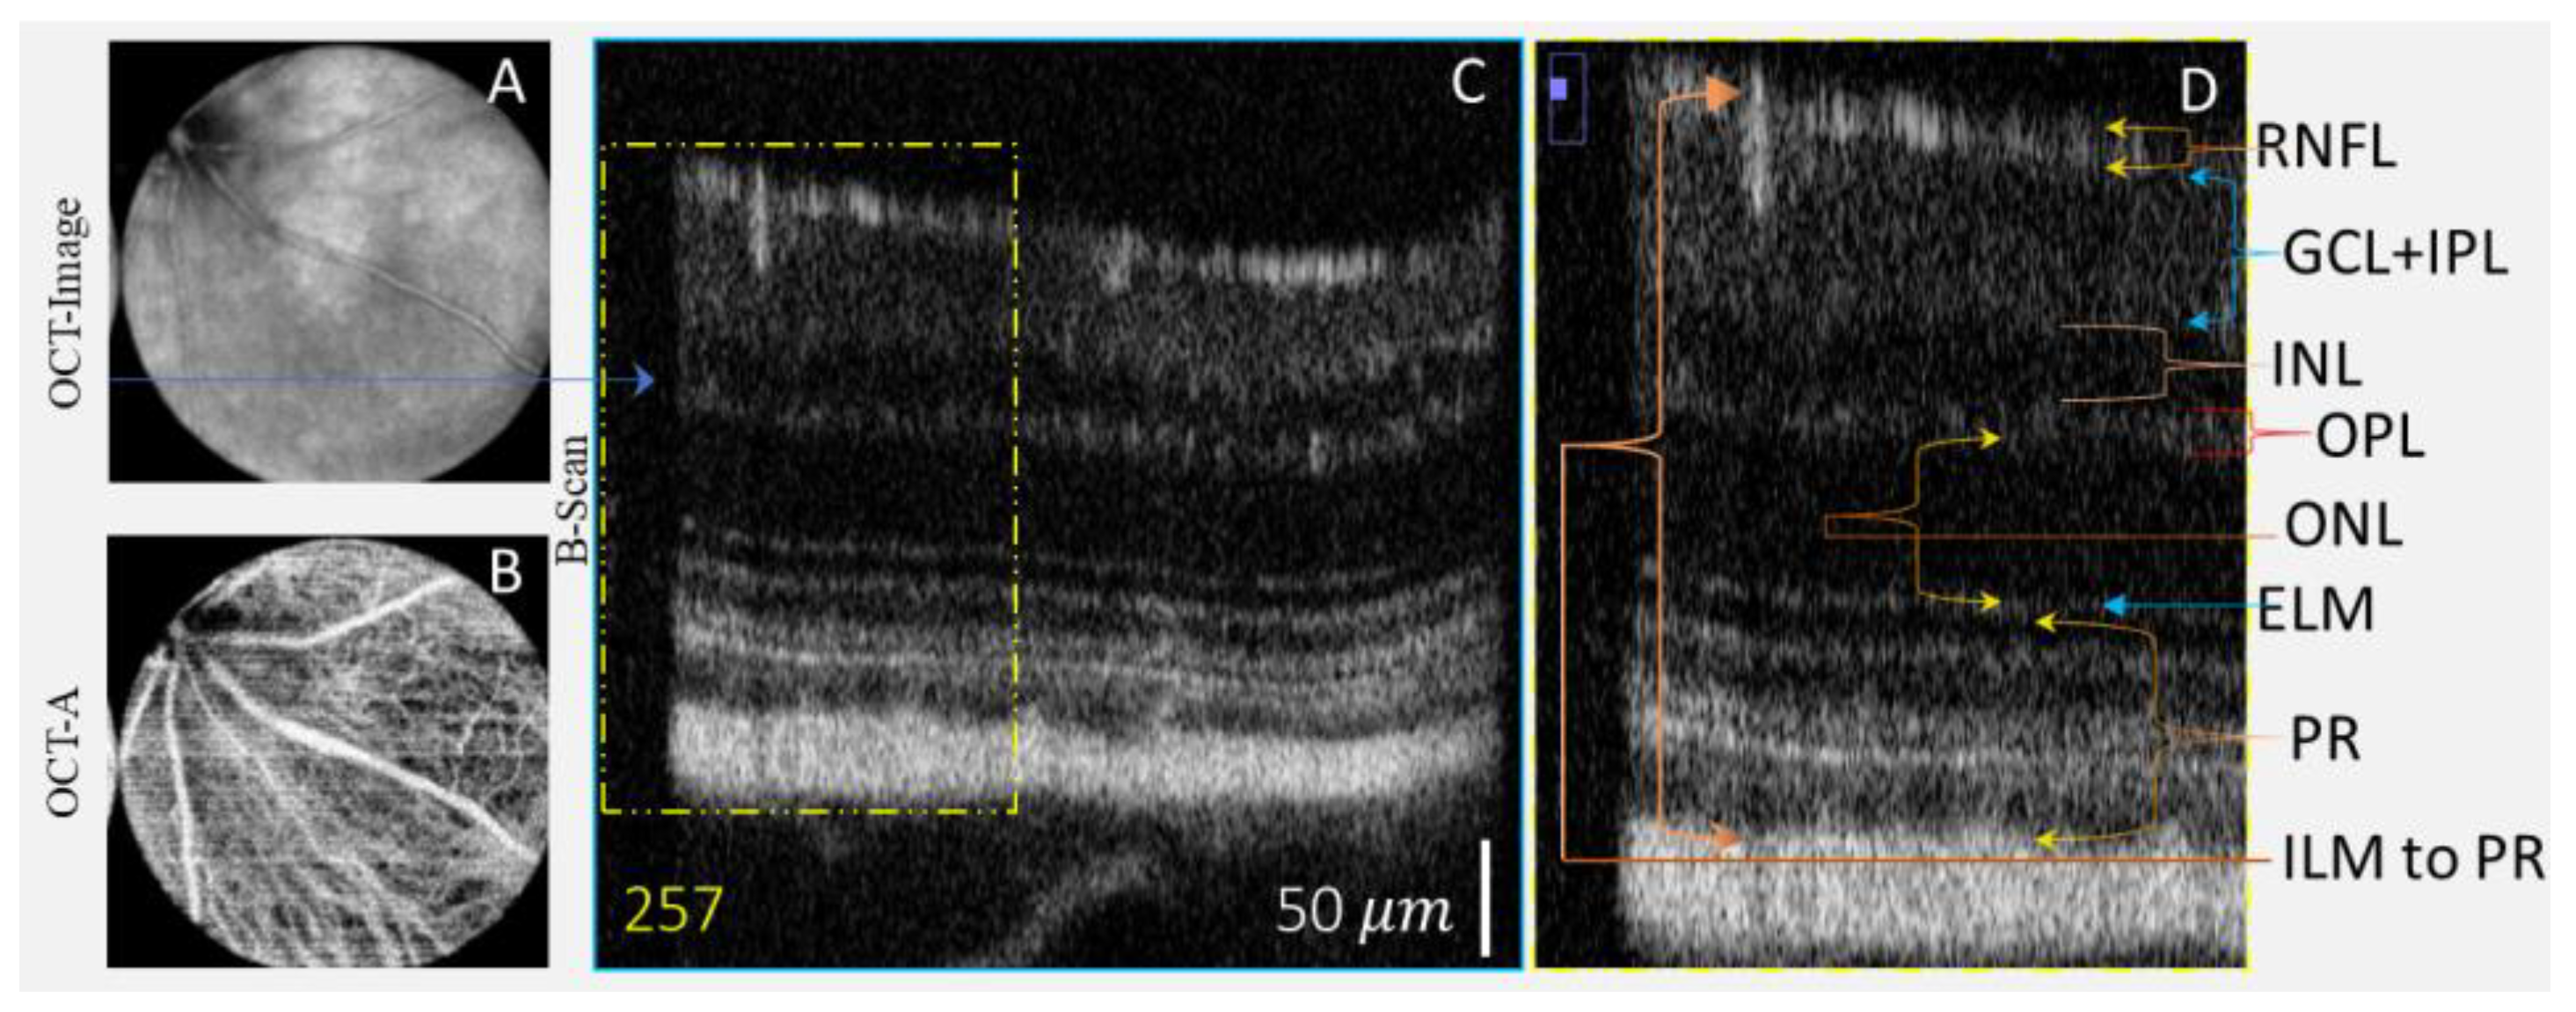

| Layer | Pixels | Thickness Estimated Using AI | Reported Thickness [33] |

|---|---|---|---|

| RNFL | 20 | 16.72 | 19.32 |

| GCL + IPL | 53 | 44.31 | 45.09 |

| INL + OPL | 25 + 21 | 20.9 + 17.5 = 38.4 | 41.92 |

| ONL | 52 | 43.47 | 46.09 |

| ELM | 12 | 10.03 | |

| PR | 81 | 67.72 | 59.86 |

| ILM to PR | 251 | 209.20 | 209.20 |